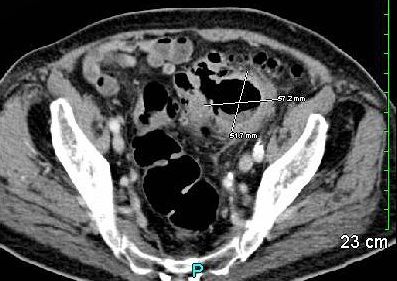

An 88-year-old man with a history of hypertension, coronary artery disease, atrial fibrillation, and hypothyroidism presented to his primary care physician complaining of malaise and a weight loss of 20 lbs over the past few months. His physical examination was unremarkable. Serum chemistries, however, revealed anemia-hematocrit, 28% (normal range, 41% - 51%)]. Abdominal CT revealed a 5- to 6-cm lesion in the pelvis suggestive of either a walled-off abscess or a diverticulum (Figure). After a surgical consultation, the patient was admitted to the hospital for further evaluation.

GCDs are detectable on abdominal x-ray and appear as large air-filled structures (the “balloon sign”). Diagnosis is most often based on CT findings, and CT imaging allows better visualization of surrounding structures.7,8 CT with water soluble contrast may help detect communication with the colon. Colonoscopy may provide visualization of other lesions but adds little additional information about GCD.3